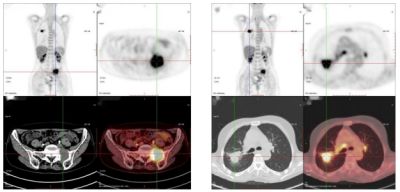

66歲,女,左側(cè)腰骶部疼痛1月,ECT檢查示:胸7、骶1及左側(cè)髂骨多發(fā)骨代謝異常,考慮腫瘤性病變,轉(zhuǎn)移瘤?

PET/CT診斷:右肺上葉后段結(jié)節(jié),代謝增高,考慮原發(fā)惡性病變(右肺上葉后段周圍型肺Ca)伴、肺內(nèi)、淋巴結(jié)及多發(fā)骨轉(zhuǎn)移。